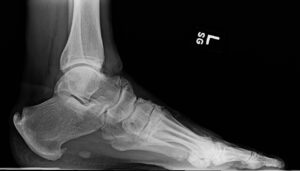

FIGURES 1: Midfoot osteophytes and joint space narrowing in left foot of 56-year-old male. (Click to enlarge.)

Midfoot osteoarthritis (OA) is a subtype of foot OA in which OA exists in one or more joints of the midfoot, most often the tarsometatarsal, talonavicular or naviculocuneiform joints (see Figure 1). OA in this region is relatively under-recognized but is a key contributor to foot pain and disability, especially in middle-to-older-aged adults.

Radiographic diagnosis of midfoot OA has traditionally utilized the Kellgren-Lawrence system.16 More recently, the La Trobe Foot Atlas was developed to identify radiographic OA across four joints (medial and intermediate cuneiform-metatarsal joints, talonavicular joint and navicular-first cuneiform joint).17

This atlas incorporates cardinal features of OA—osteophytes and joint space narrowing—allowing for four levels of severity and diagnosis of radiographic changes (scores ≥2) plus symptoms in the corresponding region. Magnetic resonance imaging (MRI), although less accessible than X-ray, may also be used with a semiquantitative scoring system that includes all joints of the midfoot.18